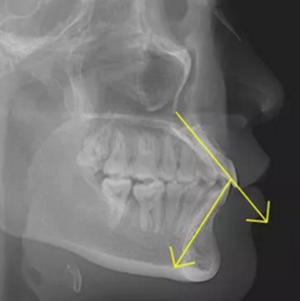

正常情況下,我們的上前牙是蓋在下前牙唇側3mm內(nèi)的,上下切牙牙軸交角為125°左右,

但前牙閉鎖合是上前牙下垂伸長,內(nèi)扣完全鎖住了下切牙,正面觀時我們??床坏较虑醒?,下切牙則常擁擠伸長咬到了上腭內(nèi)的牙齦上,上下前牙發(fā)生的交角幾近180°。

正常前牙交角

前牙閉鎖合交角